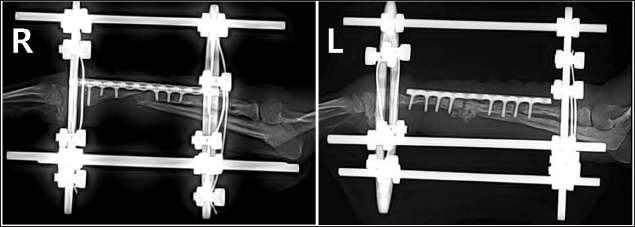

Preoperative medications for both surgeries included tramadol (5 mg/kg, IV), cefazolin (30 mg/kg, IV), famotidine (0.5 mg/kg, IV), and midazolam (0.2 mg/kg, IV). General anesthesia was induced with propofol (5 mg/kg, IV) and maintained with 1.5%–2% isoflurane in oxygen. Intraoperative analgesia was provided by a constant-rate infusion of ketamine and lidocaine. The forelimbs were then prepared for routine aseptic surgery. The entire surgery lasted 2 hours and 50 minutes. Postoperatively, cefazolin was administered for 5 days, along with tramadol and meloxicam (0.1 mg/kg, SC) for pain management. Amoxicillin syrup was prescribed for an additional 3 weeks as an antibiotic. Sutures were removed in the second postoperative week, and ongoing physical rehabilitation was implemented. External fixation devices were removed in the fourth postoperative week. Radiographic assessments showed a union of the right radius by the eighth postoperative week and the left radius by the tenth postoperative week (Fig. 4). Although forelimb ambulation remained plantigrade, the dog’s overall gait improved, enabling consistent quadrupedal movement.

Fig. 4. Lateral radiograph 10 weeks after the second surgery showing bone union progression.

Previous studies have highlighted challenges in using external fixation in toy-breed dogs due to their size, particularly in the radius (Hamilton and Langleyhobbs, 2005). However, based on the author’s clinical experience with successful CEF applications, this study initially applied CEF for temporary fixation to promote the reconstruction of lysed bone and stabilize surrounding soft tissue. Rehabilitation was performed to maintain joint function, promote vascularization, and enhance muscle mass until a second surgery was conducted. Although radiographic evaluation revealed no signs of union at the fracture site, the frequency of forelimb use increased after temporary fixation. Six weeks after the first surgery, radiography showed increased bone thickness and a decrease in the areas of lysis. In the second surgery, the fracture was reduced using plates and screws, and CEF was applied simultaneously for 4 weeks. During the 10 weeks of CEF application, no complications such as infections or implant loosening were observed, and it provided the necessary stability to maintain alignment and regenerate the bone.